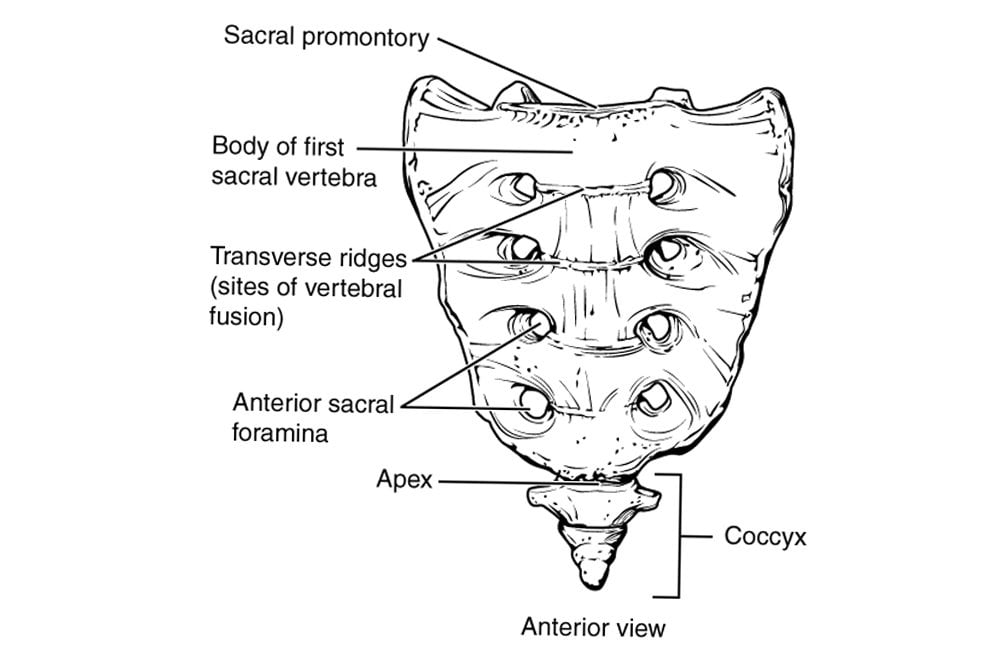

More often than not, the sacrum and coccyx are studied together as the sacrococcygeal region. The sacrum consists of 5 bones that fuse together to form a single bone, while the coccyx consists of 3-5 bones that typically do the same. In females, the sacrum is short and wide, whereas in males, it is long and narrow. The coccyx is the vestigial remnant of the tail.